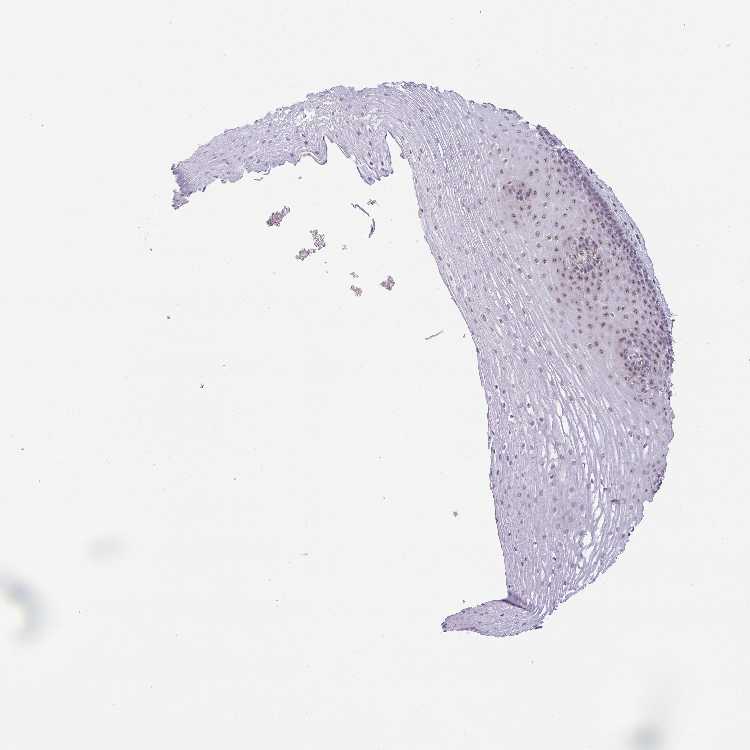

ESOPHAGUS - Antibody stainingi

Antibody staining in the annotated cell types in the current human tissue is reported as not detected, low, medium, or high, based on conventional immunohistochemistry profiling in selected tissues. This score is based on the combination of the staining intensity and fraction of stained cells.

Each image is clickable and will lead to virtual microscopy that enables deeper exploration of all samples and also displays staining intensity scores, fraction scores and subcellular localization as well as patient and tissue information for each sample.

Antibody HPA060290

Squamous epithelial cells Medium